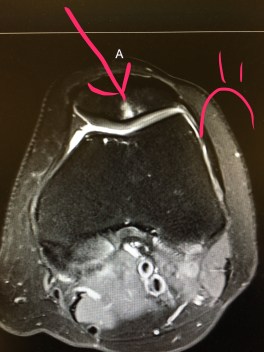

I took the usual 2 weeks off and while on vacation in Florida, insisted Sam and I go for a run. I took 3 steps and it felt like someone was stabbing my kneecaps. Like a dope, I ran/hobbled 4 miles, and was near tears the entire time (I should mention that the tears were also because I have a serious fear of getting eating by a gator). As soon as Sam and I got back to the hotel, I googled “runner knee pain” and diagnosed myself with tendinitis, arthritis, and cancer. Because, WebMD.